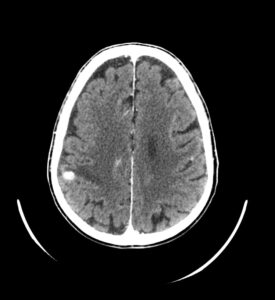

TC craneal con contraste

TC craneal con contraste IV